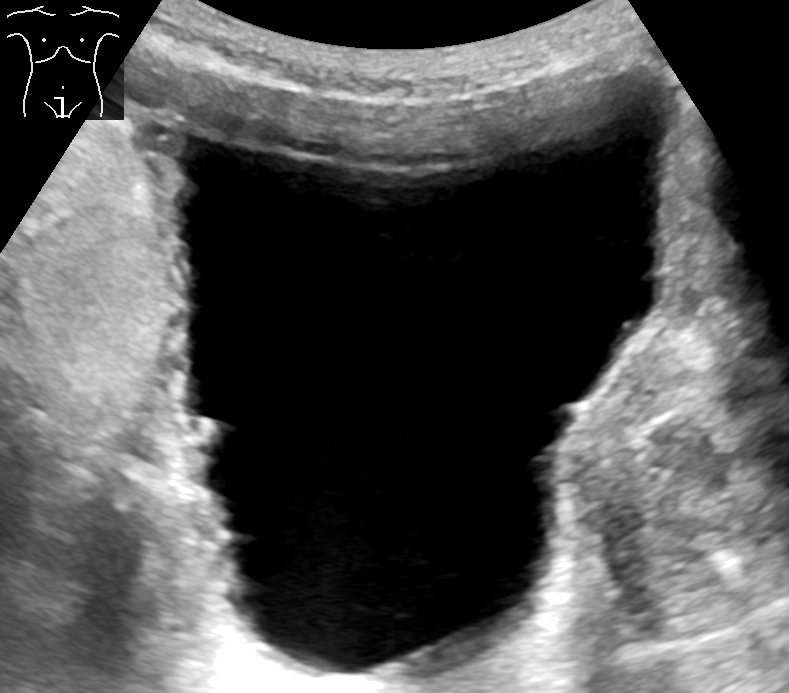

- 초음파 검사: 음파를 사용하여 신장 및 요도를 시각화하고, 배뇨 전 방광의 용량과 배뇨 후 남은 소변의 양을 평가한다. 이는 배뇨에 문제가 있는지 파악하는 데 도움이 된다.